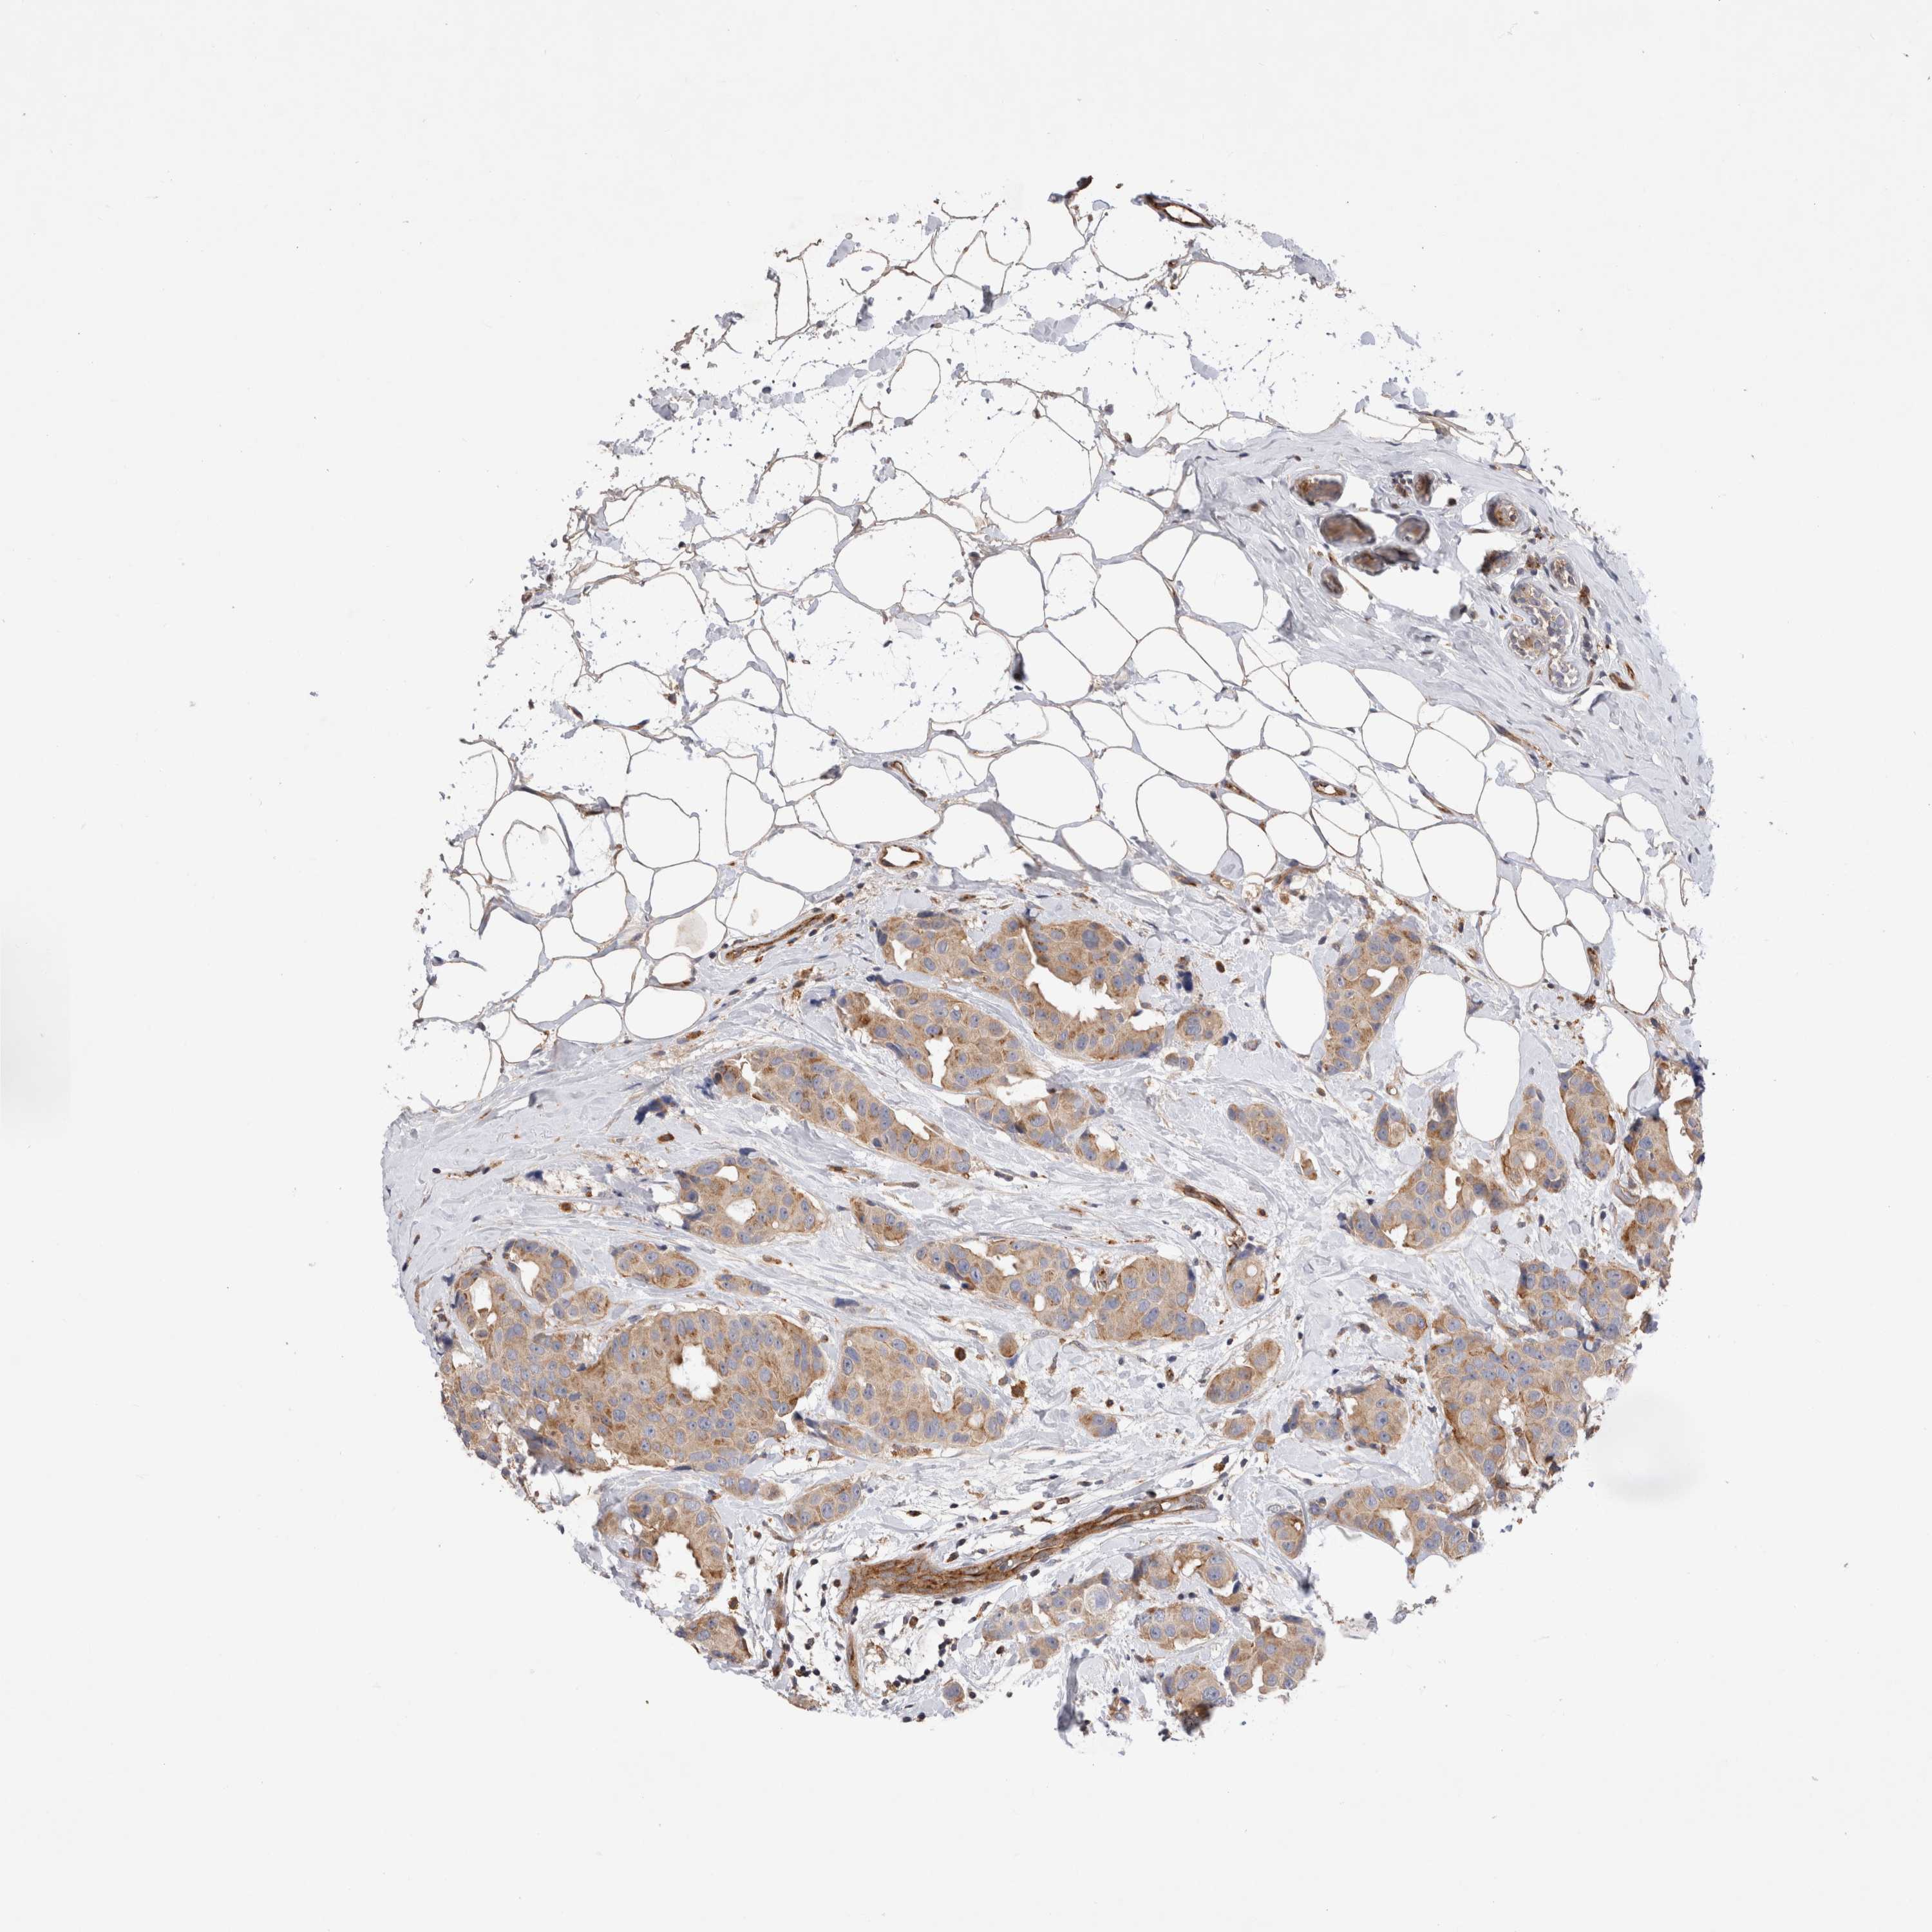

BRCA TCGA BRCA VALIDATION PROTEIN EXPRESSION